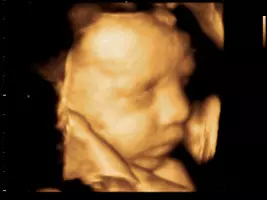

Usluge ordinacije obuhvaćaju ginekološke preglede, porodništvo, ultrazvučnu dijagnostiku, ginekološki ultrazvuk: 3D i 4D ultrazvuk. 4D ultrazvučni prikaz najčešće korišten u trudnoći, osim jasnog prikaza izgleda ploda pruža najdetaljniji uvid u morfologiju i anatomiju fetusa. Od 3D prikaza razlikuje se utoliko jer omogućuje prikaz slike u stvarnom vremenu te samim time i bolji uvid u dinamiku i stanje ploda.

3D i 4D ultrazvuk dio je onoga što na raspolaganju ima GINEKOLOŠKA ORDINACIJA DR. IGOR LONČAR. Obratite se s povjerenjem!